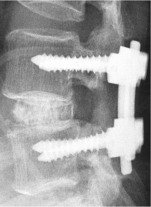

The fundamental in surgery for spinal canal stenosis is good central and root canal decompression and pre-empting instability by fusion with or without pedicle screw instrumentation.

b) Minimally Invasive Spinal Decompression and Instrumentation/Fusion

If the stenosis is predominantly of the root canal, percutaneous pedicle screw instrumentation/fusion and limited open root canal decompression can be employed to limit the extent of muscle dissection. Faster recovery is seen with this surgery.